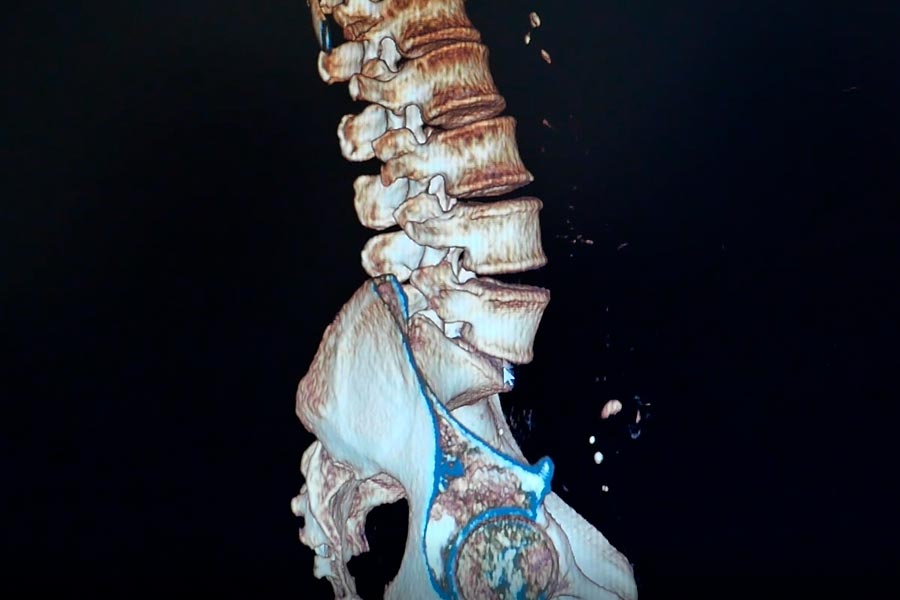

El paciente presenta una patología en el disco, con una hernia de gran tamaño. Esto comprime las raíces neurológicas, generando listesis.

Paciente con intenso dolor de una semana de evolución tras caída que no mejora con tratamiento medico ni RH. Se decide realizar una Cifoplastia.

Varón 36 años. Sufre traumatismo directo en pierna derecha con mecanismo de hiperextensión durante la disputa de un balón jugando al fútbol.

Varón de 58 años que acude a consulta con severa limitación funcional para la deambulación con inclinación y flexión postural dorsolumbar.

Nos encontramos ante un paciente varón de 58 años de edad con antecedentes personales de psoriasis. Sufrió caída desde una altura de 1,5 metros.